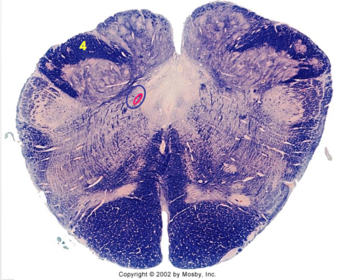

| Nucleus gracilis | |

| Nucleus cuneatus | |

| Fasciculus gracilis | |

| Fasciculus cuneatus | |

| Internal acruate fibers | |

| Lateral (external/accessory) cuneate nucleus | |

| Medullary pyramids | |

| Hypoglossal nucleus | |

| Hypoglossal nerve | |

| Dorsal motor nucleus of X | |

| Nucleus ambiguus | |

| Solitary tract | |

| Solitary nucleus | |

| ALS | |

| Medial lemniscus | |

| Medial longitudinal fasciculus | |

| Spinal tract of V | |

| Spinal nucleus of V | |

| Lateral (external, accessory) cuneate nucleus | |